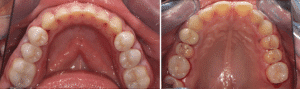

On réalise ensuite les préparations postérieures. La figure 7a est la vue initiale, la 7b la vue occlusale des préparations et la 7c la vue latérale des préparations.

Fig.7a, b, c : Préparations postérieures.

Fig.7b.

Fig.7c.

Le mock-up antérieur est toujours en bouche. On demande au logiciel de dupliquer notre empreinte de référence et on vient couper sur le duplicata les secteurs postérieurs. On scanne ensuite les préparations et notre empreinte de travail est finie. Le logiciel permet de vérifier les épaisseurs de préparation en cas de doute. L’empreinte (Fig.8a, b, c et d) est envoyée au laboratoire, le mock-up retiré et la patiente repart. Dans notre cas clinique, il n’est pas nécessaire de faire des restaurations provisoires postérieures car les tissus dentinaires exposés ont été hybridés puis protégés par du composite fluide et le reste des préparations est amélaire.

Fig.8a, b, c et d : Empreinte des préparations postérieures.

Fig.8b.

Fig.8c.

Fig.8d.